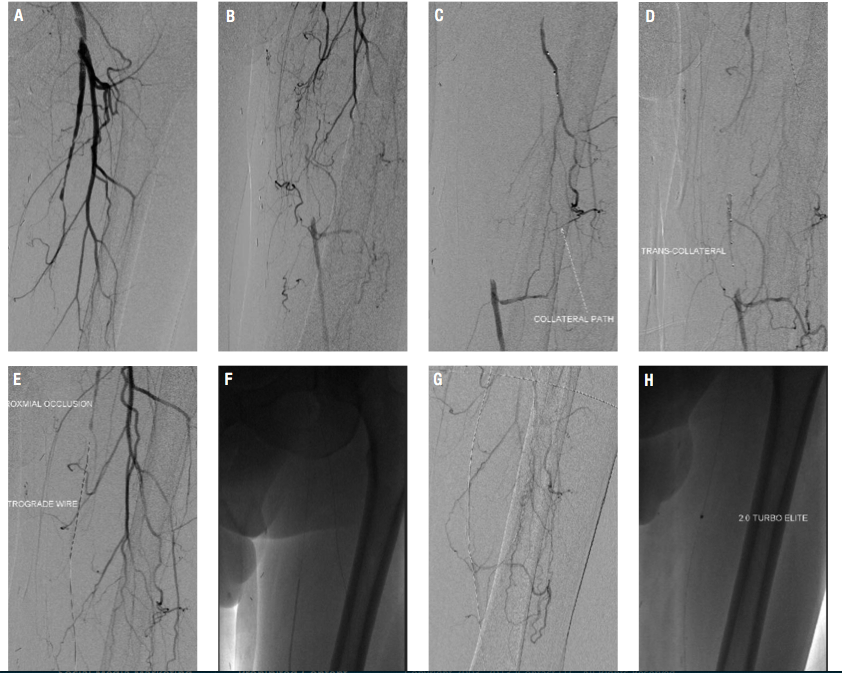

progressive claudication. He was started on a trial of medical therapy, including smoking cessation, cilostazol, and a walking program. The patient continued to smoke and despite medical therapy, complained of lifestyle-limiting claudication. He underwent diagnostic angiography and was found to have high-grade stenosis of the right SFA and complete occlusion of the left SFA (Figures 1A and 1B), and two-vessel run-off with an occluded anterior tibial artery. He was referred for percutaneous revascularization of the left SFA.

The right common femoral artery was accessed using a 4 French (Fr) micropuncture kit (Cook Medical).The sheath was upsized to a 5 Fr Avanti sheath (Cordis Corporation); using a 5 Fr IMA catheter (Boston Scientific) and an exchange-length Glidewire (Terumo Corporation), the catheter was advanced into the left common femoral. The sheath was then upsized to a 6 Fr, 45 cm Pinnacle Destination sheath (Terumo Corporation) placed in the origin of the left SFA. After administration of heparin, an Asahi Miracle Bros 6 wire (Abbott) was advanced to the cap. A Wildcat catheter (Avinger) was then advanced over the wire distally. An attempt to engage the cap resulted in deflection of the Wildcat into the collateral. Several attempts were made using the back end of the wire advanced to the distal tip of the catheter to provide more support while utilizing the Wildcat in different modes. Repeated attempts resulted in advancement of the device into the collateral branch. Next, an angled 0.18˝ QuickCross Extreme (Spectranetics) was used with a Treasure 12 guidewire (Abbott). Multiple attempts were made to advance the Treasure 12 wire into the proximal cap. It was felt this might allow advancement of the Wildcat to the cap without concern of deflecting into the collateral. Unfortunately, the proximal cap could not be penetrated secondary to the calcium as well as the angle and presence of a collateral. At this point, consideration was given to using an angled Glidewire and QuickCross catheter, and attempt a subintimal approach or bring the patient back for popliteal access. After further examination of the angiograms and angulated views (ipsilateral 20°), it was felt that there was an adequate collateral to attempt transcollateral passage of a wire. The Destination sheath was withdrawn into the left common femoral, and the wire was advanced into the collateral utilizing a Runthrough wire (Terumo) and a Finecross catheter (Terumo). Due to poor visualization of the catheter, the Finecross was exchanged for a 0.14˝ QuickCross and the wire was exchanged for a 300 cm Asahi Fielder wire (Abbott). Selective injection was then performed of the collateral through the QuickCross (Figure 1C). The Fielder wire was negotiated through the collateral and into the distal lumen of the SFA (Figure 1D). The 0.14˝ QuickCross was then advanced into the SFA in a retrograde manner and the wire was changed to an Asahi Confienza wire (Abbott). The wire was advanced in a retrograde manner through the calcified lesion to the proximal cap (Figure 1E). The cap could not be penetrated, despite attempts with several wires (Confienza, Cross-It, Pilot 300). At this time, the 0.14˝ QuickCross was exchanged for an 0.18˝ QuickCross through the collateral in a retrograde manner. The wire was then changed to a Treasure 12 wire, which easily penetrated the cap. The wire was then advanced into the left common femoral artery and exchanged for a Runthrough wire. Several attempts were made to rewire the sheath or rewire an angled catheter. This was in order to externalize the wire and proceed with revascularization. These attempts were unsuccessful. Multiple attempts were made to snare the wire by utilizing a 2.0 mm loop snare (eV3). This also was unsuccessful. At this point a 2.0 x 100 Coyote balloon (Boston Scientific) was advanced via the collateral into the lesion in a retrograde manner. The vessel was dilated at 6 atm for 20 seconds (Figure 1F). At this point, a Fielder wire was easily advanced in an antegrade manner into the tibioperoneal vessel and then exchanged for a RunThrough wire (Figure 1G). A 2.0 TurboElite Laser fiber (Spectranetics) was then utilized to debulk and modify the plaque as well as facilitate balloon delivery (Figure 1H). The lesion was

predilated with a 6.0 x 100 AngioSculpt scoring balloon (AngioScore) at 4 atm x 2 minutes (Figure 1I). This was performed in an overlapping manner. This was then followed by placement of a 7.0 x 150 SMART stent (Cordis), which was postdilated with a 7.0 x 100 Sterling balloon (Boston Scientific) at 4 atm (Figure 1J). Final angiography demonstrated brisk flow without embolization, perforation, or dissection. The sheath was withdrawn and a Mynx closure (AccessClosure) was performed in the right groin. The patient was discharged home the following morning without incidence.